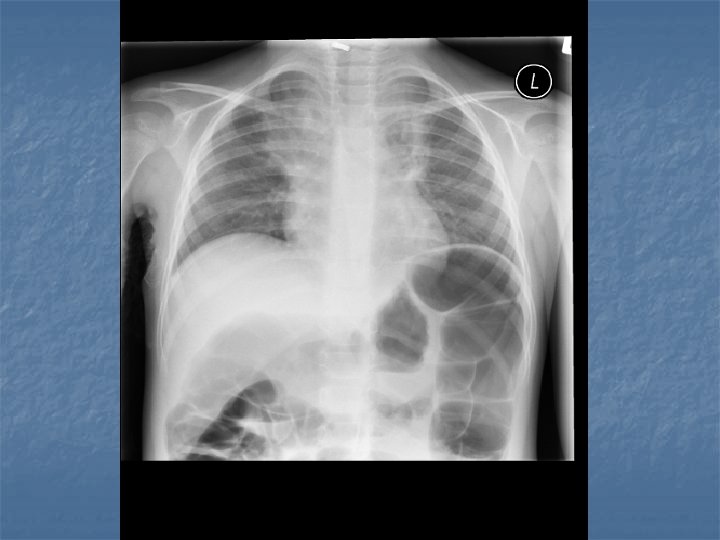

Case AJ: 11 yo male n n n N/V/D x 1 day 6 x vomitting, 2 x diarrhea Periumbilical abdo pain “Dizzy” Rhinitis, cough 38 C, HR 117, RR 28, 105/75, 96% RA

AJ’s Exam n n n Pale Small cervical nodes Abdo exam nontender No indrawing Decreased breath sounds RLL, crackles

Pediatric CAP n n Bronchopneumonia – acute inflammation smaller bronchial tubes and peribronchiolar alveoli Pneumonitis Syndrome – Infants 1 – 3 months old, afebrile with cough, tachypnea and progressive respiratory distress. n n CXR shows diffuse pulmonary infiltrates and air trapping Single or mutlipathogens involved

CXR Summary n In combination with physical exam, do a CXR when: Questionable dx n Admitting pt n <3 y with fever >39 C and WBC >15 n Complicated pneumonia suspected n

CXR Findings VIRAL n Peribronchial thickening n Diffuse interstitial infiltrates n Hyperinflation BACTERIAL n Subsegmental, segmental or lobar infiltrates n Air bronchograms n Round pneumonia in early S. pneumo n n M. pneumo diffuse infiltrates out of proportion to clinical findings (or bronchopneumonia infiltrates in lower lobes) Bilateral reticulonodular interstitial infitrates

n n n 50% bacterial pneumonia will have lobar infiltrate Can also see alveolar infiltrates Round pneumonia seen with S. pneumo